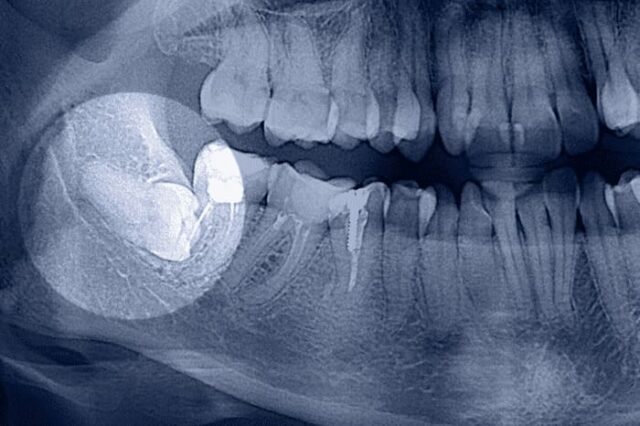

- после сложного удаления “восьмерок” (ретинированных, дистопированных, с искривленными корнями);